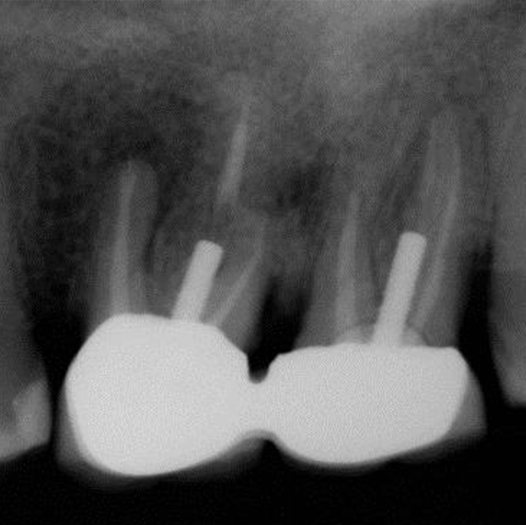

Before

After

Before Root Canal treatment

After Root Canal treatment